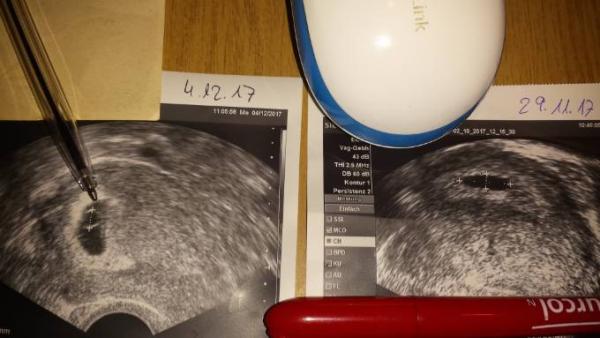

Was ist das eigentlich wo die Mine vom Stift ist?????? Das ist im rechten Bild nicht da gewesen

Ich sehe auf deinem Bild ehrlich gesagt nur den Dottersack. Und der Embryo ist wirklich in dieser Woche schon relativ groß gegenüber dem Dottersack. Ich kann dir bis jetzt nur Vergleichsbilder von meiner letzten Schwangerschaft zeigen. Da siehst du wie es in der Woche eig aussieht. Natürlich drücke ich dir trotzdem die Daumen, dass alles gut ausgeht!!! Versteh mich bitte nicht falsch. Ich wünsche dir natürlich nur das Beste!!! Bild links bei 7+4 Bild rechts bei 8+6

Hallo. Ich schleiche mich mal kurz ein da mich die dusskusion doch sehr interessiert. Mal eine ganz andere Frage. Könnte es möglich sein das deine ss noch garnicht so weit ist wie deine Ärztin sagt? Im Vergleich von Bild am 29.11 bis heute sieht man ja schon eine Entwicklung aber die würde ich eher auf die 5-6 Woche einstufen und nicht Anfang 8te. Ich würde an deiner stelle abwarten. Wenn der HCG sinkt wie vor mir schon erwähnt wurde dann leitet de Körper eh alles von allein ein.

Was dann aber immer immer noch komisch ist, ist das man den Dottersack bei ihrer ersten Untersuchung schon mal gesehen hat. Da sagte der Arzt ja damals alles zeitgerecht. Dann hatte sie Kontrolle eine Woche später, da sah man dann nur die Fruchthülle. Siehe Bild was sie gezeigt hat. Dazu sagte der Arzt dann schon da stimmt was nicht, aber abwarten. Dann Termin heute, man sieht wieder den Dottersack, aber nicht mehr. Klar, zu dem Bild bei der Untersuchung davor wäre es eine gute Entwicklung. Dann würde ich sagen ist jetzt in der 6.Woche. Aber da man ja schon den Dottersack sah wo sie wirklich in der 6.Woche war, dann in der 7.Woche gar nichts mehr und jetzt in der 8.Woche nur den Dottersack wieder, sagt mir mein Gefühl da kann was nicht stimmen. Das tut mir dann natürlich leid und auch ich hoffe auf ein Wunder. Deshalb wirklich eine 2.Meinung einholen